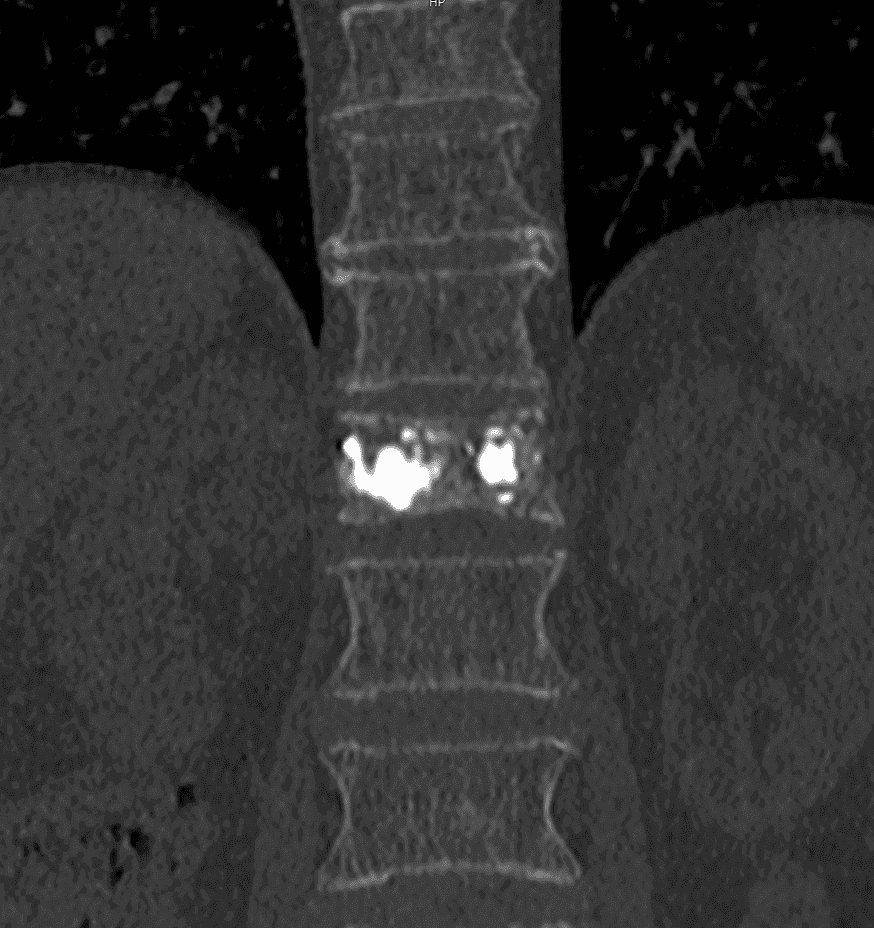

Injection du ciment

Pour assurer la stabilité de l’ensemble, du ciment osseux est injecté de manière contrôlée autour de l’implant, garantissant ainsi la consolidation et la pérennité du résultat.

L’implant SPINEJACK est une technique de radiologie interventionnelle, innovante et peu invasive, qui offre une alternative aux méthodes traditionnelles telles que la vertébroplastie ou la kyphoplastie. Cette procédure consiste à insérer un implant métallique à l’intérieur de la vertèbre fracturée. Une fois positionné, l’implant est déployé pour restaurer la hauteur et la forme normale de la vertèbre, ce qui aide à réaligner la colonne et à réduire la compression sur les structures nerveuses. Par la suite, un ciment osseux est injecté pour consolider l’implant et stabiliser la fracture.